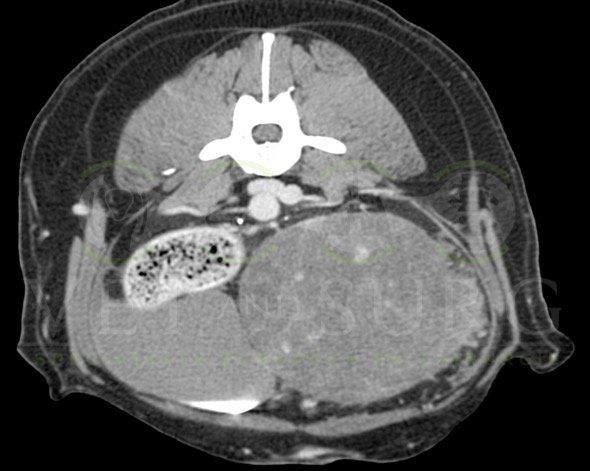

Obstruction urétérale chez un chat Sacré de birmanie de 8 ans

A l'échographie abdominale, une dilatation de la cavité pyélique rénale gauche est mise en évidence, avec présence de calculs obstructifs dans l'uretère gauche.